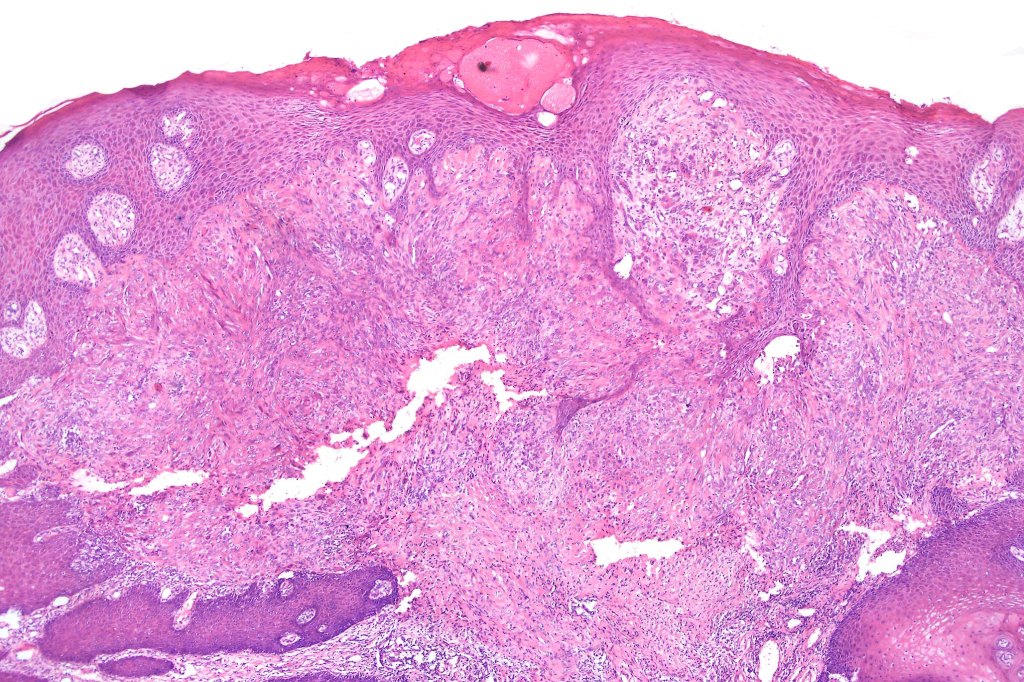

•Sharply circumscribed (begins and ends with a nest), symmetrical dome-shaped lesion. Symmetry is both horizontal and vertical (see image below)

•Wedge-shaped with the base uppermost or sometimes plaque-shaped silhouette

•Matures with depth-often best recognized at scanning/low power magnification & readily confirmed with S100 or MART1

•Maturation implies nest size and cell size diminishing with depth, at the base, the infiltrate may have a single cell infiltrating pattern

•Hyperkeratosis & acanthosis, sometimes very marked

•Superficial vascular ectasia very frequently present

•Junctional nests often vertically orientated, dyscohesive with a surrounding retraction artifact